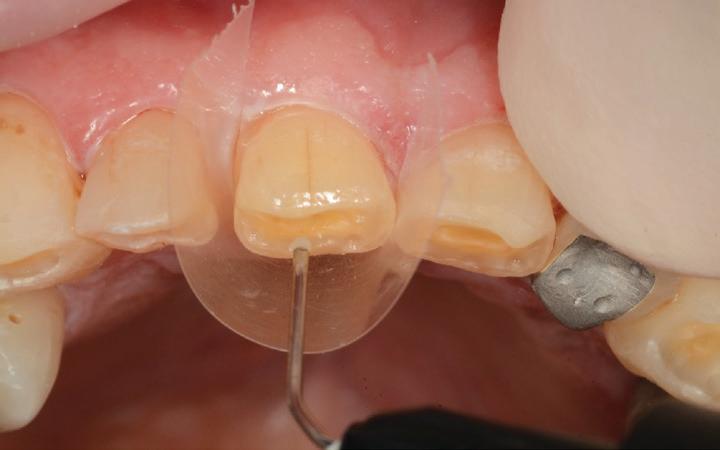

The maxillary anteriors were then isolated one at a time, and a selective etch adhesive protocol was used with the adhesive OptiBond™ Universal by KerrTM (Fig. 8).

Flowable composite (HerculiteTM Ultra Flow, Shade A2) was then applied to the dentine surface and cured, to complete the adhesion process (Fig. 9). The tooth was then restored with a new nanohybrid composite material, HarmonizeTM by KerrTM

Each buildup was completed by firstly adapting a mylar matrix strip to the palatal and interproximal surfaces and a thin layer of A2E (Enamel) shaded composite was then applied and cured (Fig. 10). The matrix was then removed and the centre of the tooth was then built up with A3D (Dentine) shaded composite – to the approximate volume that natural dentine would occupy (Fig. 11).